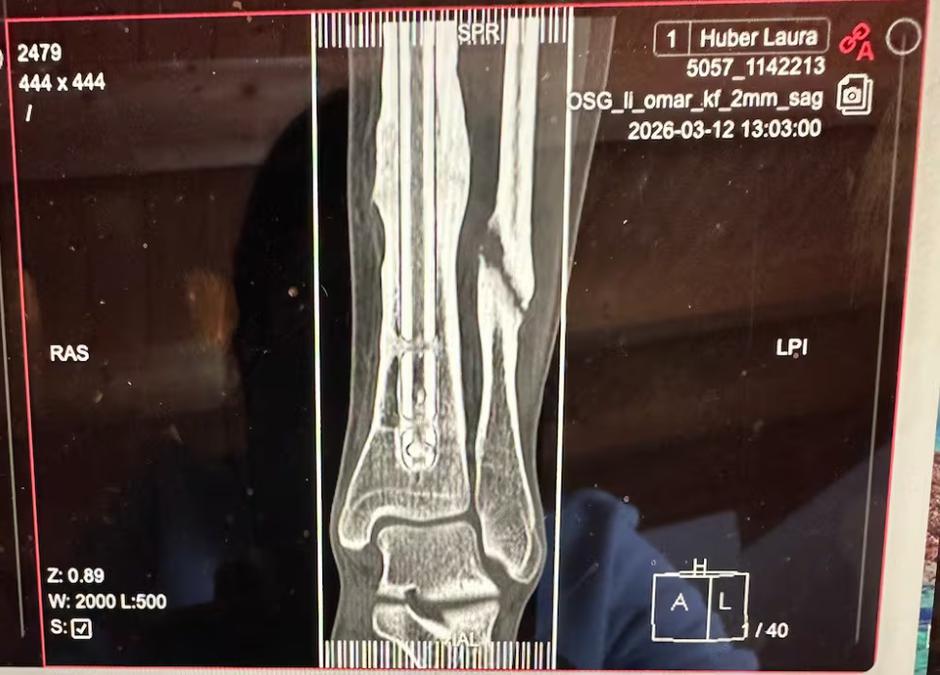

Izvidi so bili naravnost šokantni, izkazalo se je namreč, da je mlada smučarka odpeljala 44 tekem z zlomljeno mečnico!

"Ko so mi pokazali rentgen, sem bila šokirana," je za Blick povedala specialiska za hitre discipline, ki je medtem že prestala operativni poseg za učvrstitev kosti s ploščico in vijaki. "Ponoči me zelo boli, a se bolečina iz dneva v dan zmanjšuje," je povedala.

Huber je februarja lani doživela nesrečo na treningu, v kateri je utrpela zlom golenice ter poškodbo mečnice. Golenico so ji operirali, pri mečnici pa se je po posvetu z zdravniki odločila za konzervativno zdravljenje z injekcijami, kar naj bi pripomoglo k hitrejšemu celjenju kosti. "Injekcije so pomagale, golenica se je lepo zacelila, mečnica pač ne."